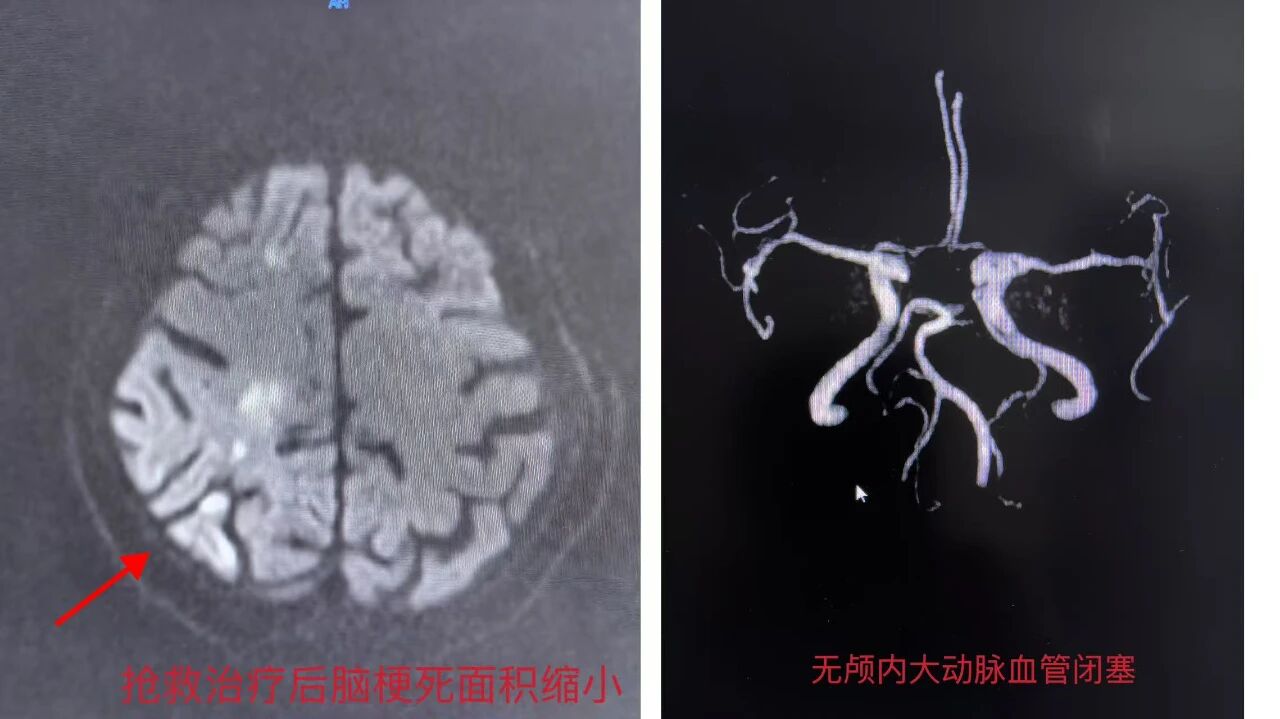

近日,我院神经内科成功救治一名85岁高龄的急性重症脑梗死患者。从入院时神志不清、肢体瘫痪、生命垂危,到治疗后第4天能够口齿清晰、自行端碗吃饭,该患者的快速康复创造了一个生命的奇迹,充分彰显了我院神经内科在脑血管病急危重症救治领域的精湛技术与雄厚实力。

患者陈奶奶,今年已85岁高龄。发病当日,她在家中突然昏倒,家人发现时已神志不清,无法言语,并出现多次呕吐,小便失禁。紧急送至我院急诊后,查体发现其左侧上下肢肌力为0级,意味着完全瘫痪,丝毫不能动弹。头颅CT等检查迅速确诊为“急性大面积脑梗死”。患者年龄高、症状重、病情进展迅猛,随时可能因脑水肿加重出现脑疝,危及生命,救治形势极其严峻。

面对如此高危的病例,神经内科团队没有丝毫犹豫。时间就是生命!科室立即启动脑卒中绿色通道,医护团队争分夺秒,在极短时间内完成了病情评估、影像学研判及家属沟通。尽管患者属于静脉溶栓的相对禁忌人群,但团队凭借丰富的临床经验和精准的风险效益评估,为患者制定了包括紧急溶栓/取栓桥接、强化药物治疗及后续综合管理在内的个体化、创新性治疗方案。

奇迹发生:精准治疗显奇效,四日康复创佳绩

治疗过程紧张而有序,在医护团队的密切监护和精心治疗下,奇迹开始一点点出现:· 治疗后第3天:陈奶奶的意识状态明显好转,反应灵敏,能够与人进行清晰的言语交流。更令人惊喜的是,原本完全瘫痪的左侧手脚已经能够自主进行伸屈活动。· 治疗后第4天:康复的捷报再次传来——陈奶奶竟然可以自己稳稳地端起碗吃饭了!这一场景让家属激动不已,也让所有参与救治的医护人员倍感欣慰。从卧床不起到生活基本自理,短短四天时间,患者的功能恢复超出了所有人的预期。